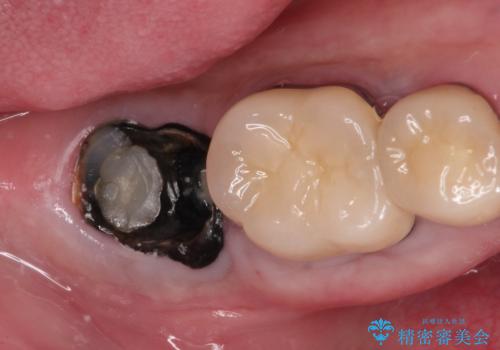

- 「他院で治療した被せ物が外れた」を主訴に来院された患者様です。診査診断を行い歯の保存が困難だったため抜歯後、インプラントで治療しました。